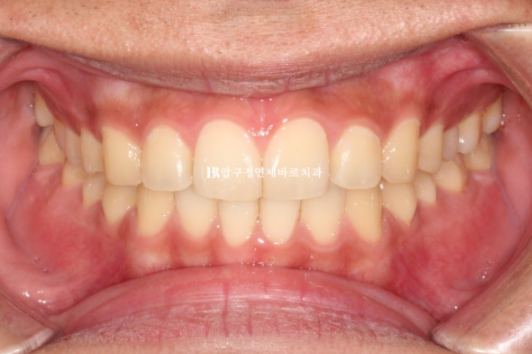

24.10

걱정하시는 교합도 좋습니다.

인비절라인은 교합이 안 좋게 끝난다 라는 편견을 깨기 위해 노력합니다.

배열도 좋습니다.